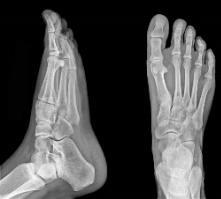

For testing, grayscale and color photos are obtained. The simulations are run on MATLAB R2021b with a Windows 10 operating system and 8 GB of memory. The test images are shown in Figure 6(a) to Figure 6(f). As a result, these cipher images provide no relevant information about the plain image. The plain images retrieve as it is after the decryption process. As we can see, our scheme can be implemented quickly. Table 1 shows the results of evaluation metrics between input and cipher image and time of encryption. Table 2 shows the results of evaluation metrics between the input image and retrieved image and the time of decryption. The tables display the results of the encryption and decryption of each image using three chaotic maps, to compare these results later and to determine the best map in the case of encryption and decryption.

(a) (b) (c) (d) (e) (f) Figure 6. Plain grayscale images with different sizes: (a) 512×512, (b) 600×600, (c) 900×900, (d) 1024×1024, (e) 612×612, and (f) 500×500